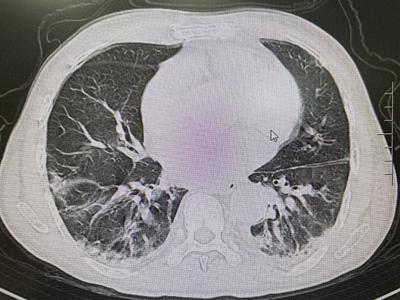

時間回到2020年元月,風濕免疫科收住一位71歲的老年男性患者,四肢肌肉無力已經5月余伴反復發(fā)熱1月,雙上肢不能抬舉,雙下肢不能下蹲站起,行走困難,面頰部、眶周、雙手背出現(xiàn)鮮紅色皮疹,腫脹明顯,伴有明顯胸悶、氣短,進食及吞咽困難,全身多關節(jié)疼痛。該患者先后在當?shù)鼐驮\兩家大型三甲醫(yī)院的多個科室,因為診斷不明,始終治療無效。歷經周折來到風濕免疫科后,科室團隊經過綜合評估診斷為“皮肌炎并重度肺間質病變”。

(2020年1月 肺部HRCT)

經近2年的門診規(guī)范化診療,病情完全得以控制并處于持續(xù)的穩(wěn)定狀態(tài)。近期復查肺部HRCT示間質性炎癥已完全吸收,肺功能檢測也基本正常,患者皮膚、肌肉、關節(jié)癥狀全部消除,現(xiàn)日常生活已恢復常態(tài),從事以前一樣的勞作。為此,老人及家屬充滿了感激之情。

(2021年12月 肺部HRCT)